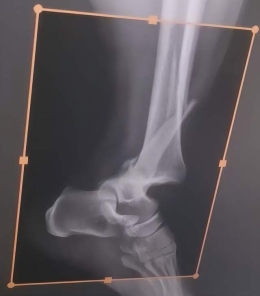

日照市康复医院骨科手术案例在日常生活和交通出行中,意外伤害时有发生。及时、专业的医疗干预,往往是决定患者功能恢复程度的关键。案例介绍月前,在村中骑电动车的王女士(化名)不小心被垂落的电缆勒伤颈部并摔倒...